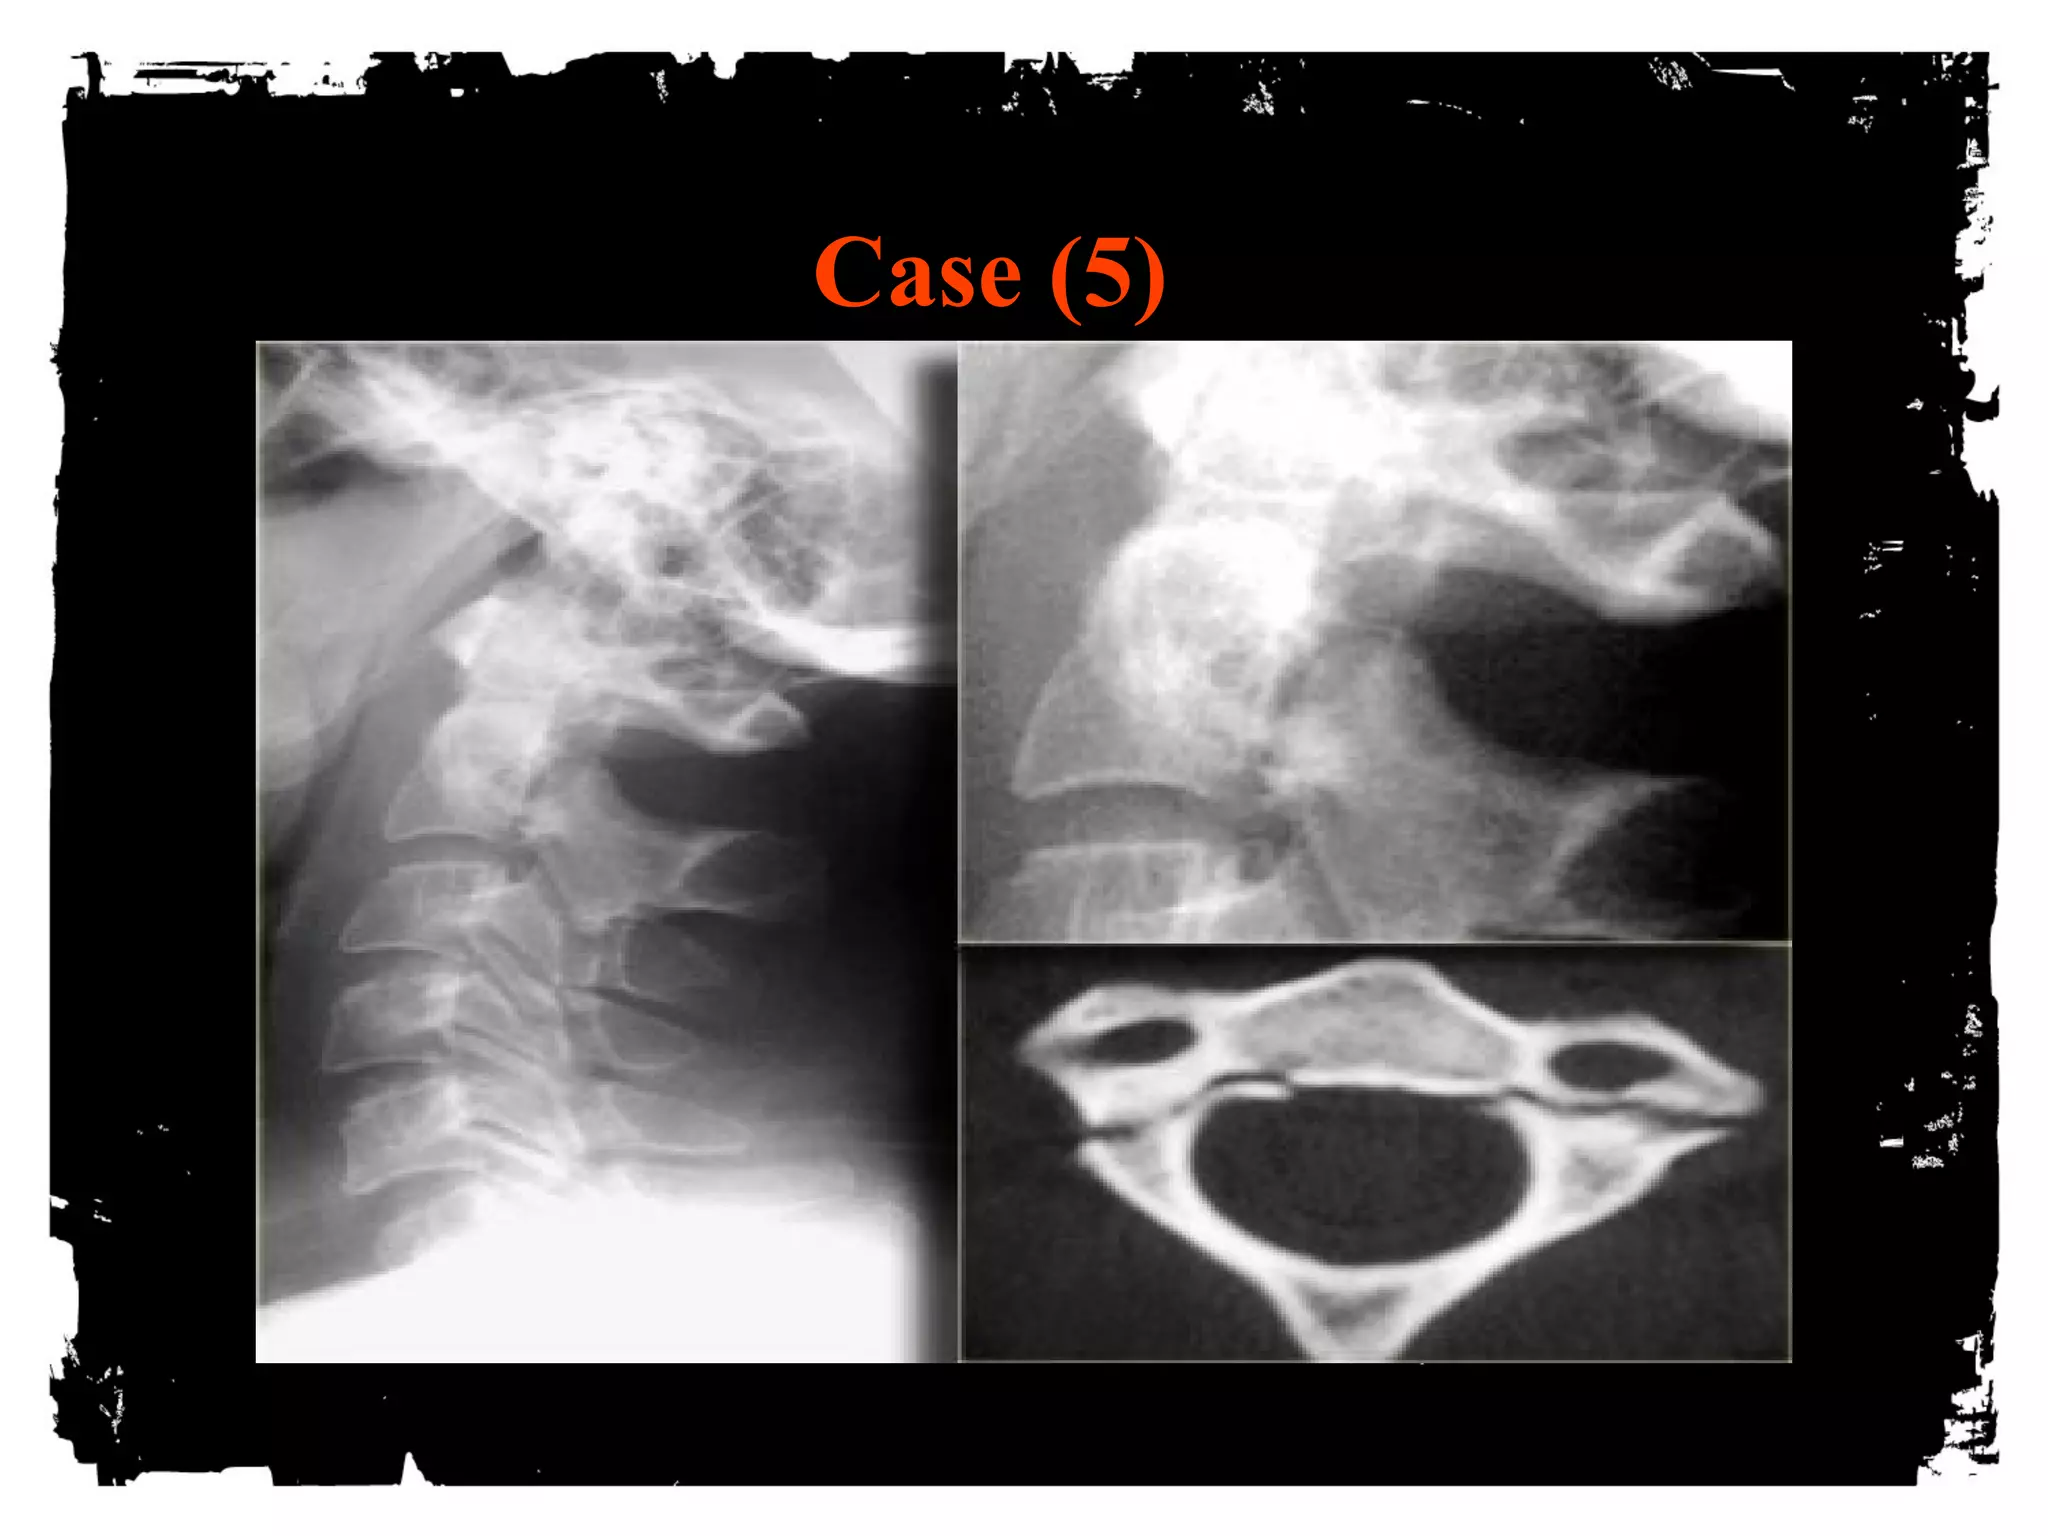

Case (5)

Hangman’s fracture

Most common cervical spine fracture

Usually hyperextension

Unstable, however seldom associated with cord

injury (AP diameter of spinal canal greatest at C1/C2

level and # pedicles allow decompression)

Hangman’s + uni/bilateral facet dislocation: high rate

of neurologic complications